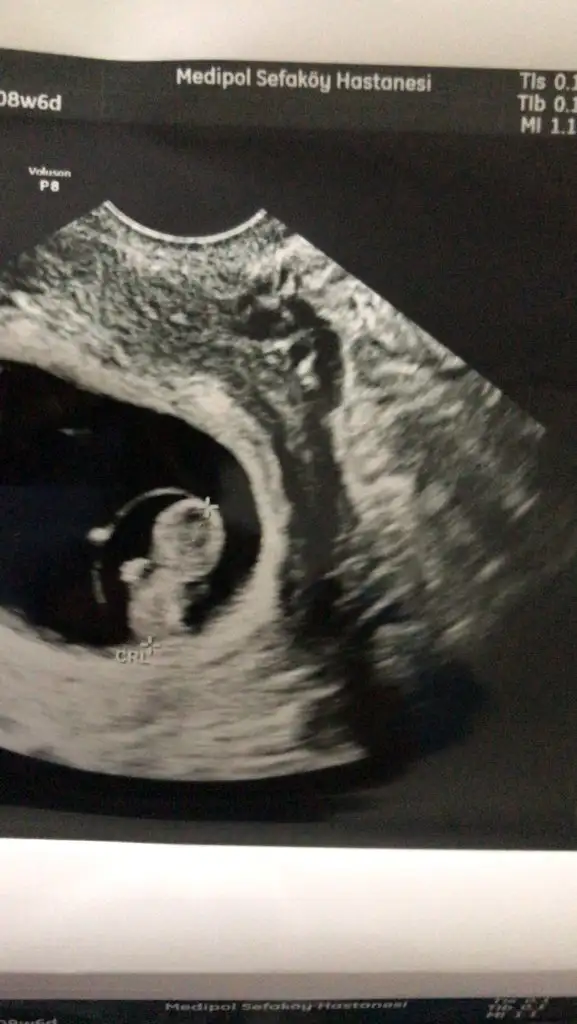

Ne kadar tatlı duruyor oyEki Görüntüle 3239315 Kızlar merhaba 8. Haftayı bitirmiş bulunmaktayım. Dün forumda okuduğum olumsuz şeyler vs beni çok kötü yaptı bebek iyi mi değil mi emin olmak istedim az az da ağrılarım oluyordu burada da sormuştum zaten sizlerinde oluyor mu diye emin olmak için dr gittim.

Tatlım bu arada hurma yemek bizler için sağlıklı değil pek. Senin de aklında olsunEki Görüntüle 3239315 Kızlar merhaba 8. Haftayı bitirmiş bulunmaktayım. Dün forumda okuduğum olumsuz şeyler vs beni çok kötü yaptı bebek iyi mi değil mi emin olmak istedim az az da ağrılarım oluyordu burada da sormuştum zaten sizlerinde oluyor mu diye emin olmak için dr gittim.